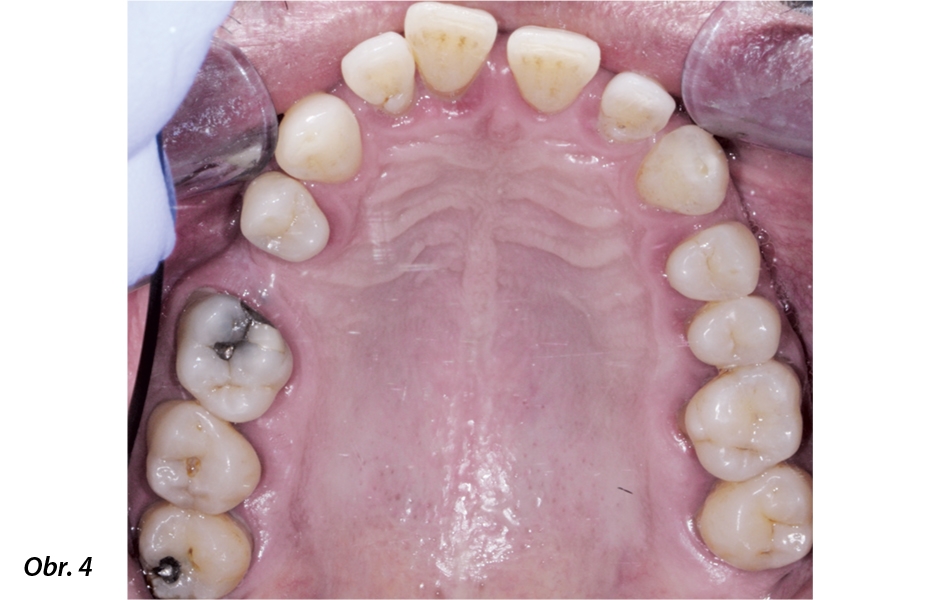

49letý pacient přišel na naše oddělení se stížností na krvácení dásní a rozestupování frontálních zubů (obr. 1–5).

Fotografická dokumentace počátečního stavu před parodontologickým ošetřením